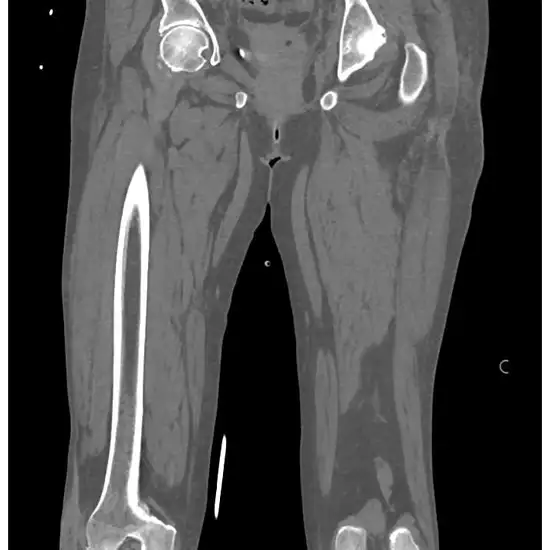

NCCT Right Leg is an imaging scan to visualize the bone and soft tissue of the right leg.

NCCT (non-contrast computed tomography) screening of the Right Leg is a non-invasive radiology test used to evaluate the condition of the Right Leg and surrounding tissue. NCCT Right Leg is done to look for the conditions of the Right Leg and the surrounding area.